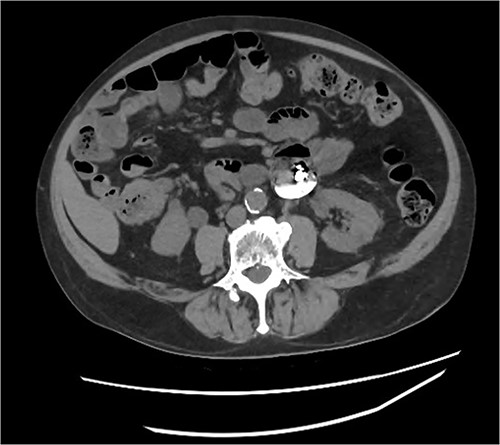

Abdominal CT identifying one hearing aid in a jejunal diverticulum 3 weeks after initial presentation – axial view.

Abdominal CT identifying one hearing aid in a jejunal diverticulum 3 weeks after initial presentation – coronal view.